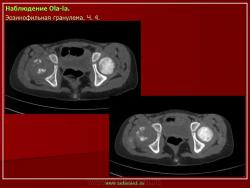

Из опубликованных наблюдений н сайте.